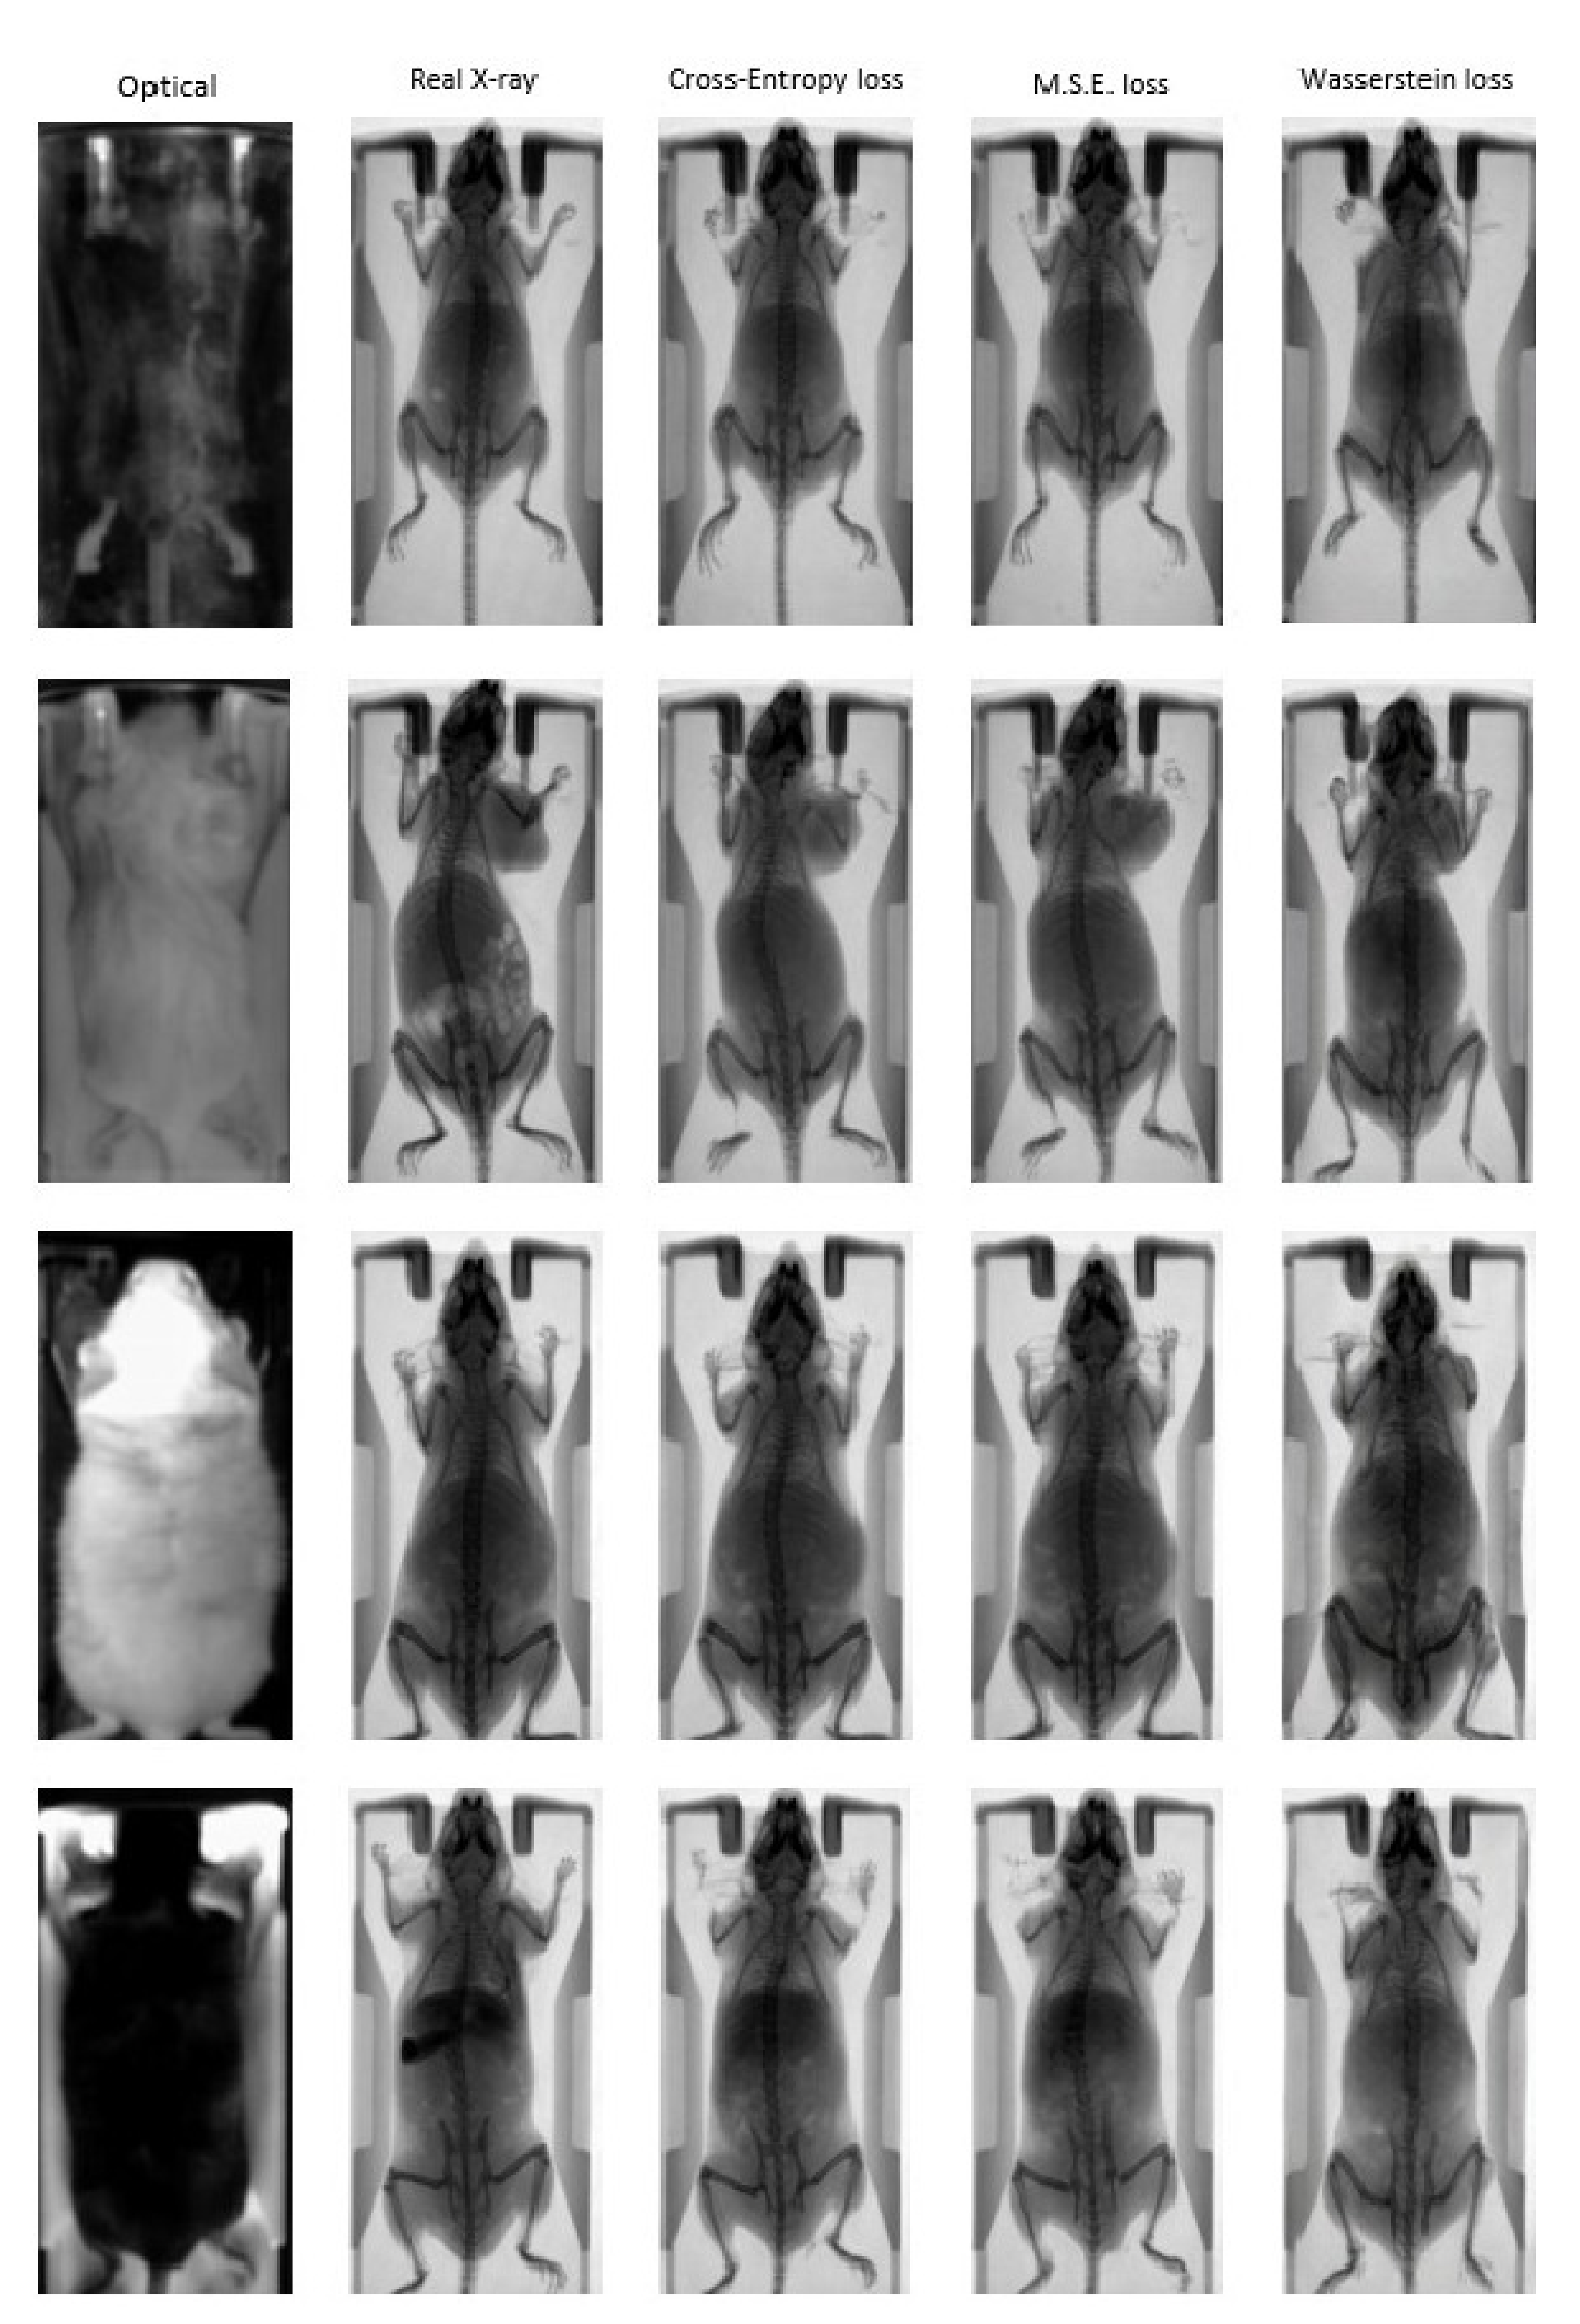

3. Results

3.1. Quantitative Evaluation

3.2. Animal Mapping during In Vivo Molecular Imaging Experiments

4. Discussion and Conclusions